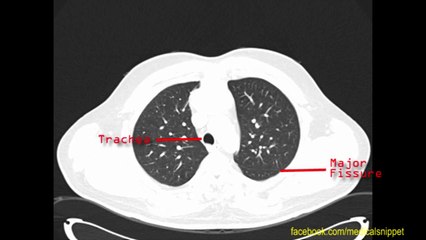

5mm Left Lobe lung Nodule Skinny Core Co-axial Biopsy